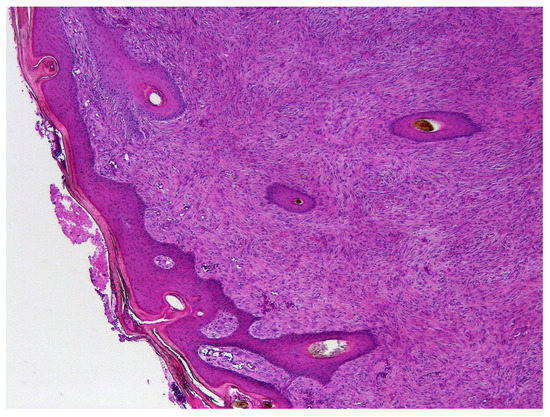

3. Results